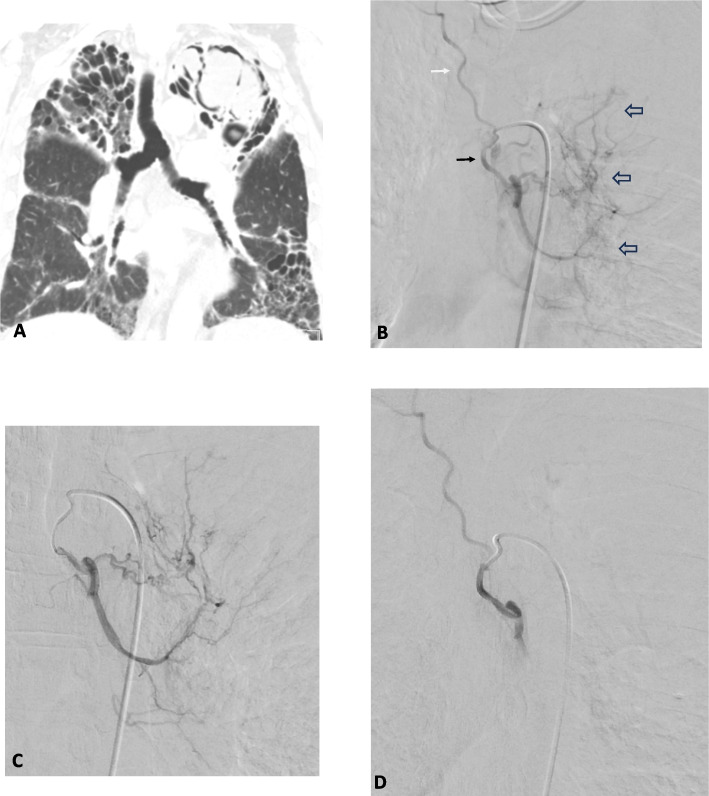

Abstract Image